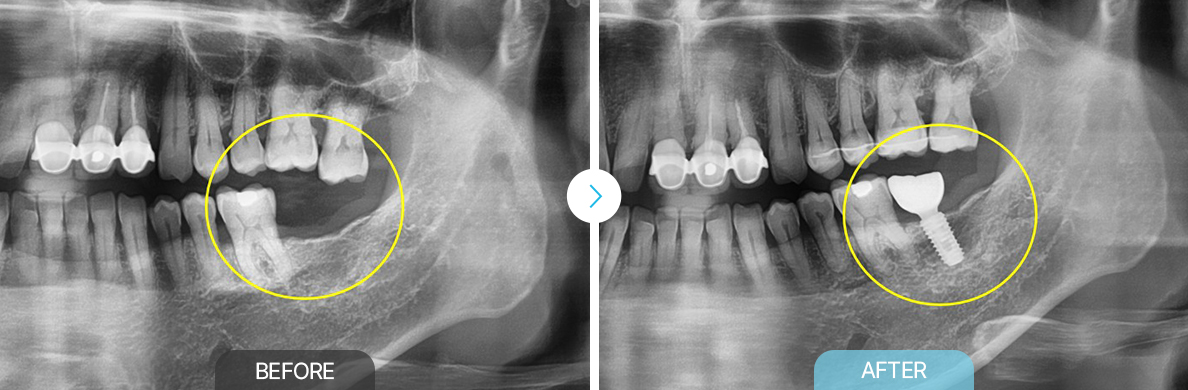

BEFOREAFTERBEFOREAFTER